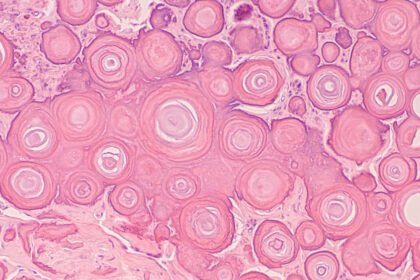

Meningioma: Understanding Symptoms And Treatments